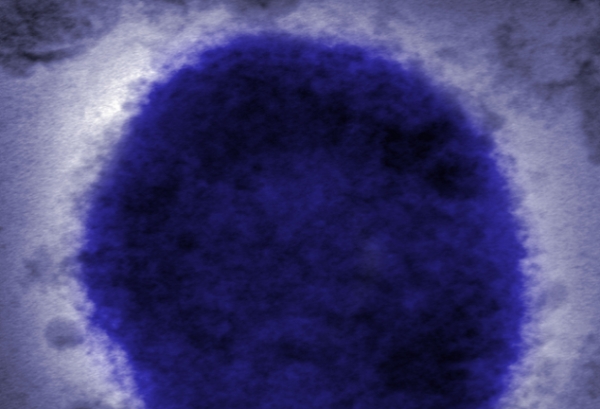

وعادة ما يظهر الفيروس، وهو أحد أقارب الجدري، كمرض خفيف لا يستمر أكثر من بضعة أسابيع.

ويمكن أن يسبب الحمى والصداع والطفح الجلدي، والتي قد تسبب بثورا مماثلة لتلك التي تظهر مع انتشار جدري الماء.